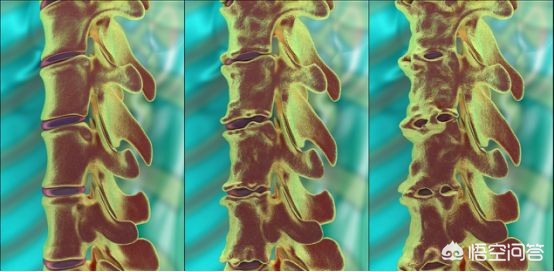

当病情比较严重的时候也会影响到病人的眼部、肺部以及肌肉和骨骼,是一种自身免疫性的疾病。大家看下图应该就会明白这个疾病的病理发展过程。

强直性脊柱炎的患者的病理发展过程就相当于有一个坏蛋想要破坏我们的身体,于是他就会拿大量的水泥涂抹在我们脊柱的周边,慢慢的让我们的脊柱变成一根棍子,不再像以前可以做各个方向的旋转,屈伸,当患者晚期的时候,会出现明显的脊柱形态的改变,而且连提鞋或者是弯腰这样最基本的动作都无法完成。